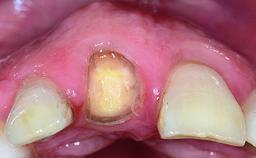

A healthy 37-year-old female patient was referred for a consultation on the replacement of missing tooth 21 with an implant-supported restoration. She stated that several years previously the tooth had been traumatically avulsed following a motor vehicle accident. The tooth was replaced with a three-unit fixed partial denture (FPD) immediately afterwards. Over time, she became disillusioned with the FPD and looked for a different option, including orthodontic therapy. She presented still in her orthodontic appliances, with the pontic sectioned free from the FPD but attached to the archwire. Her orthodontist felt that orthodontic treatment had been successfully completed, but nevertheless referred her before removing the appliances in case adjustments were necessary.

Abutment Type CAD/CAM

Prosthesis Type FDP